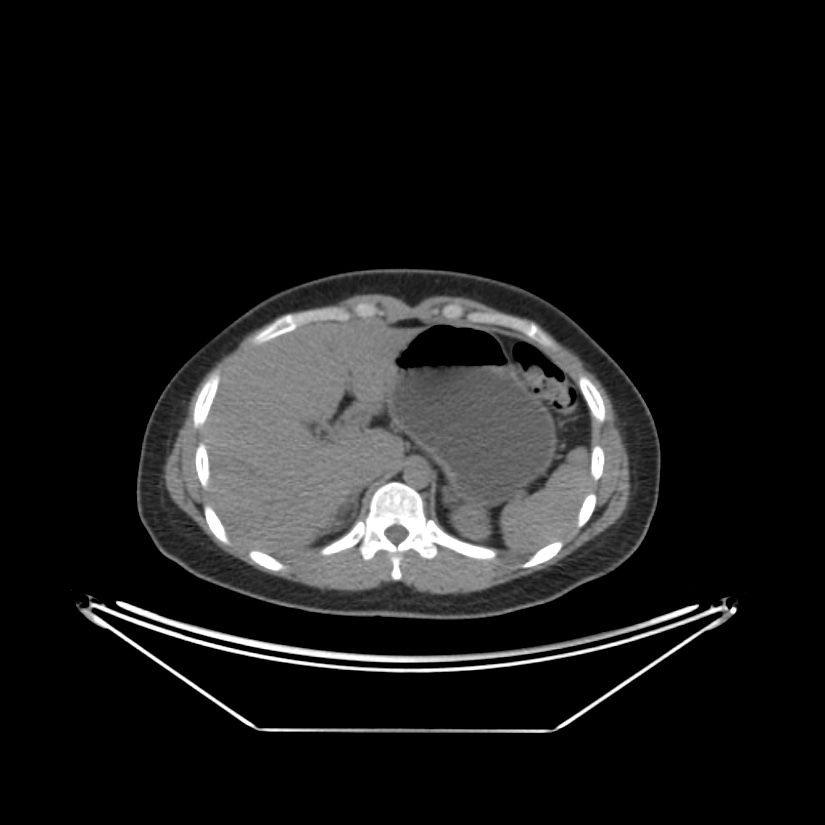

Paciente de 66 años con antecedente de pancreatitis, tomografía control.